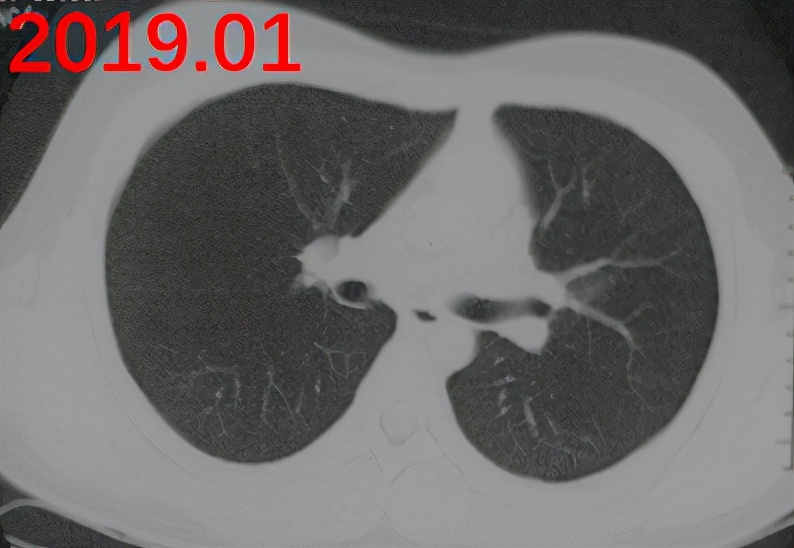

2020.10:头晕,伴有左侧肢体麻木2个月;头颅核磁:肿块伴环形强化;PET-CT:颅内,肺部,皮下,腹腔、左侧股骨颈;代谢活性增高多发结节灶;血嗜酸性粒细胞3.6*10^9/L,总IgE大于5000kU/L。